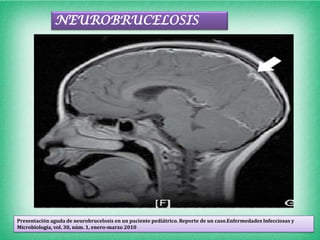

Estas imágenes corresponden al estudio contrastado T1 en cortes sagitales, donde se observa una importante captación

meníngea en relación con datos de meningitis en el nivel del lóbulo parieto-occipital y tentorio cerebeloso como señalan

las flechas.